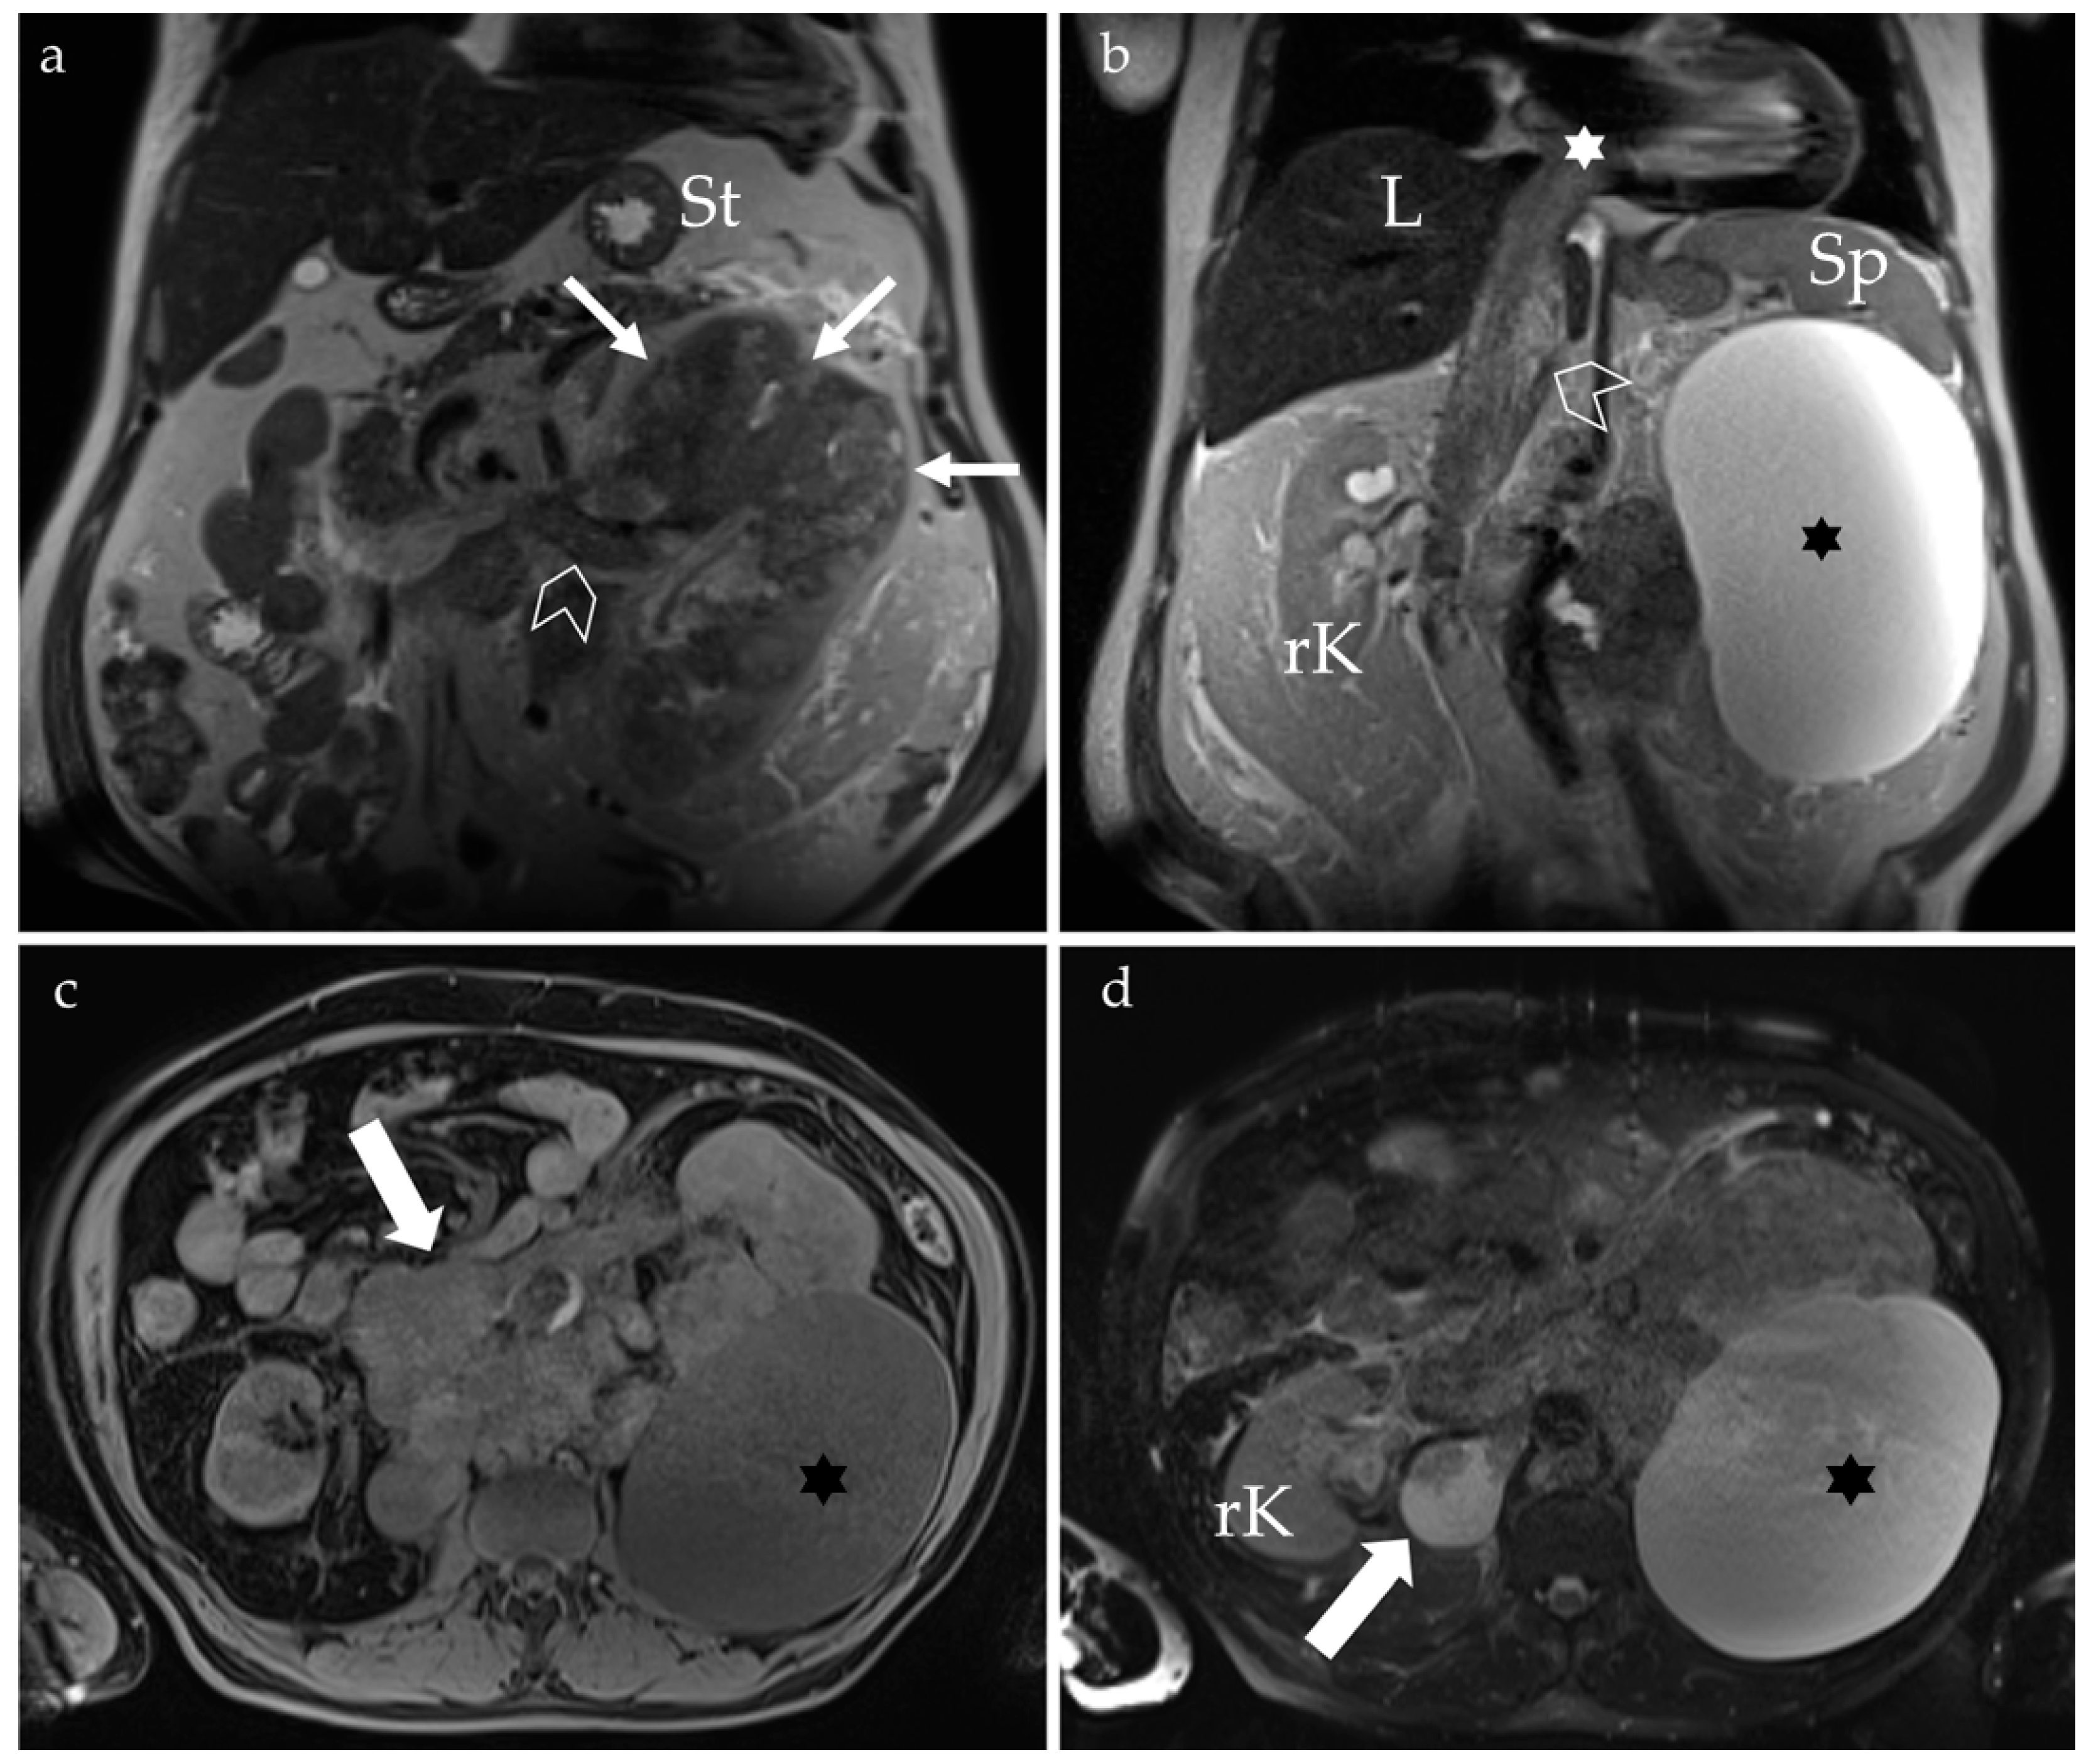

1.3. Diagnostic Assessment

2.2. Inferior Vena Cava Thrombosis